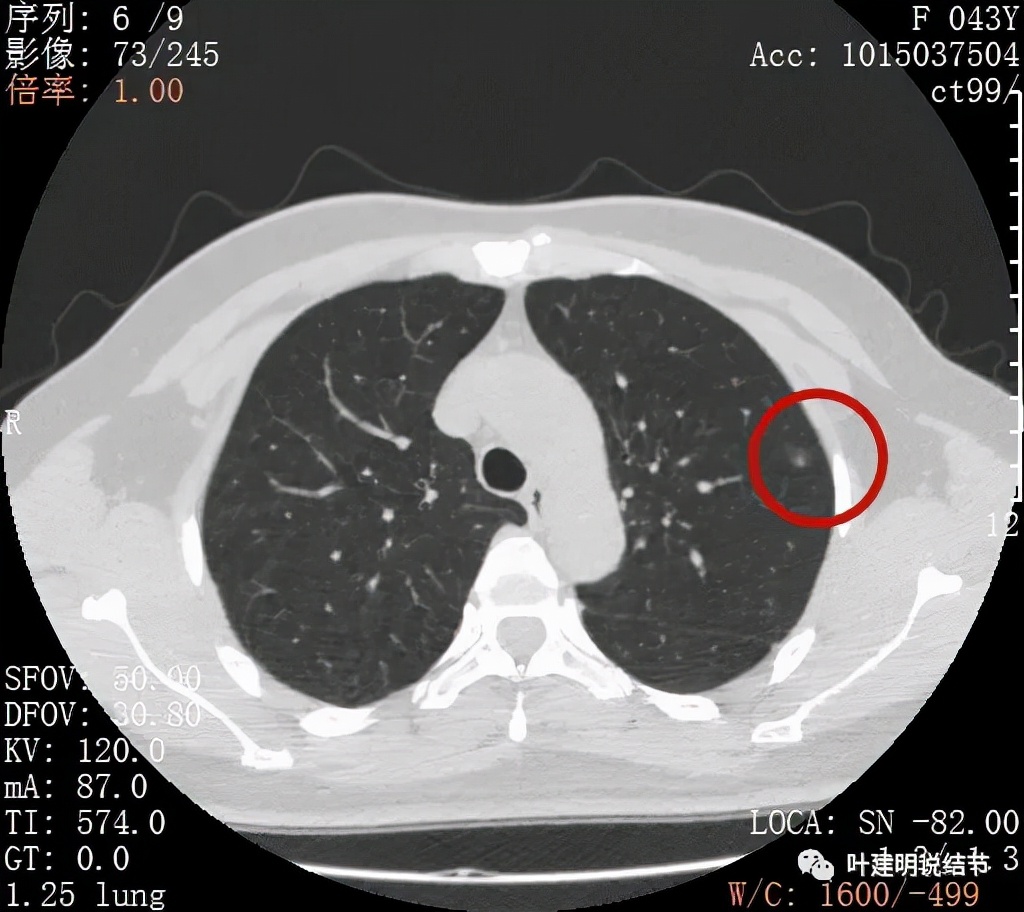

病灶密度较低,膨胀性略,瘤肺边界在靶扫描上还是显得有些清晰的

病灶瘤肺边界清,密度偏低,有点散,但有微小血管进入(桔色箭头)